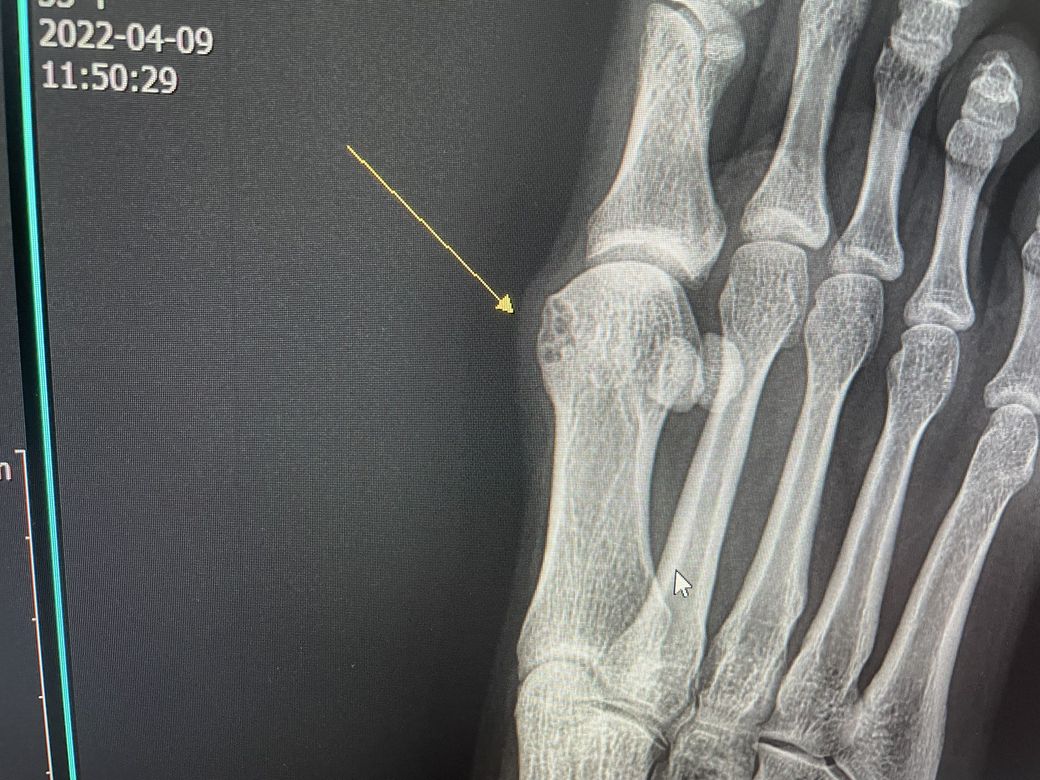

통증이 있어 ct를 찍어봤더니 뼈에 구멍이 난 것 처럼 나왔습니다. 자세한건 mri를 찍어봐야한다고 들었습니다.왜 저렇게 구멍이 난것처럼 나온걸까요 .. 어떤증상인지 궁금합니다! mri를 찍어봐야 알 수있는걸까요?

• 1. 올리신 사진은 CT 사진이 아닌 x-ray 검사 사진입니다.

2. 엑스레이 소견만으로는 구체적으로 해당 소견이 무엇 때문인지 파악하기 어렵습니다.

3. MRI 등의 정밀 검사를 해 보아야만 더 자세히 알 수 있을 것으로 보입니다.

상기 방사선은 구멍이 난 것이 아닙니다.

3차원의 사진을 2차원으로 표현해서 그렇게 보이는 것이지 구멍이 난 소견이 아닙니다.

통풍이 있는경우 해당 소견과 비슷한 모습이 보이기도 합니다.

구멍이 난건지 파인건지 골융해가 일어난건지는 잘모르겠습니다.

그쪽이 외부랑 가장 가까운부분이니까 자주 충격을 받아 변형되었을수도있고요

그냥 모양이 그렇게 생겼을수도 있고 염증이 생겨서 골수가 부었을수도 있습니다.